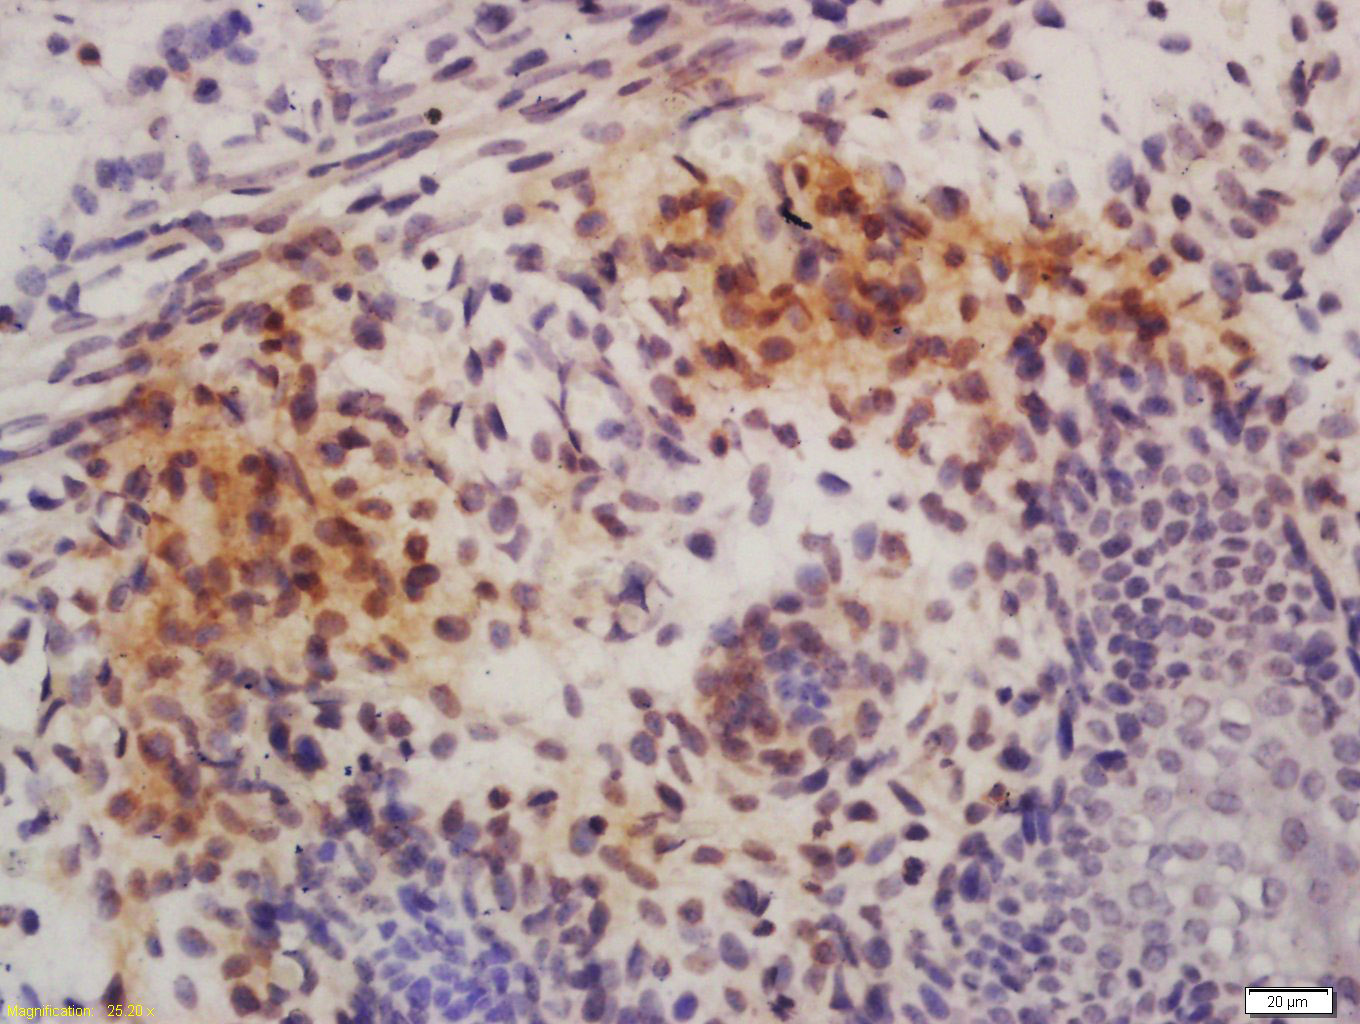

| 英文名称 | phospho-c-ABL (Tyr245) Rabbit pAb |

| 产品应用 | WB=1:500-2000, IHC-P=1:100-500, IHC-F=1:100-500, IF=1:100-500 Not yet tested in other applications. |

| {IHC-P} | {1:100-500} |

Antigen retrieval: citrate buffer ( 0.01M, pH 6.0 ), Boiling bathing for 15min; Block endogenous peroxidase by 3% Hydrogen peroxide for 30min; Blocking buffer (normal goat serum,C-0005) at 37℃ for 20 min;

Incubation: Anti-H1FOO Polyclonal Antibody, Unconjugated(bs-10335R) 1:200, overnight at 4°C, followed by conjugation to the secondary antibody(SP-0023) and DAB(C-0010) staining

Primary: Anti- phospho-c-ABL (Tyr245) (bs-10355R) at 1/1000 dilution

Secondary: IRDye800CW Goat Anti-Rabbit IgG at 1/20000 dilution

Predicted band size: 124 kD

Observed band size: 124 kD